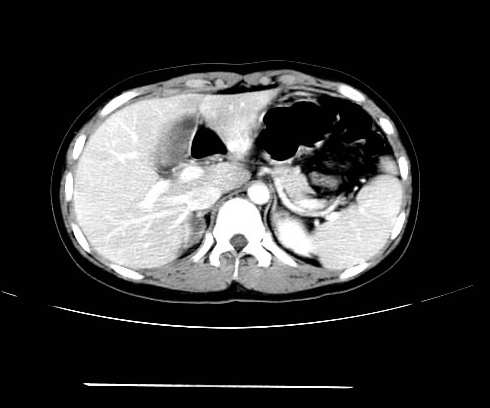

女 16岁  右上腹痛一天,无其他不适

肿块最大径位于十二指肠降段与水平段移行处,并且与肝脏压迹呈“0”形征,可以考虑位于肝外并与胃肠道关系紧密,考虑胃肠道间质瘤(gist)可能较大,须除外神经节起源肿瘤。

肿块与十二指肠关系密切,支持间质瘤诊断.肝脏与结肠均为受压改变.

右下腹巨大肿快,密度不均匀,内见坏死低密度区,边界清楚,与周边胀器明显有分界,未见强化,多考虑来源于间叶组织的良性肿物.

病灶巨大,少部分向肠腔内生长,大部分向长腔外生长。其密度不均匀,增强显示明显不均匀强化,并见有大片状始终不强化的不规则坏死液化区。虽然病灶中上部形态尚可,病人又如此年轻,但中下部形态、密度、强化特点强烈提示为恶性病灶。综上,我考虑本病例为:恶性胃肠道间质瘤。